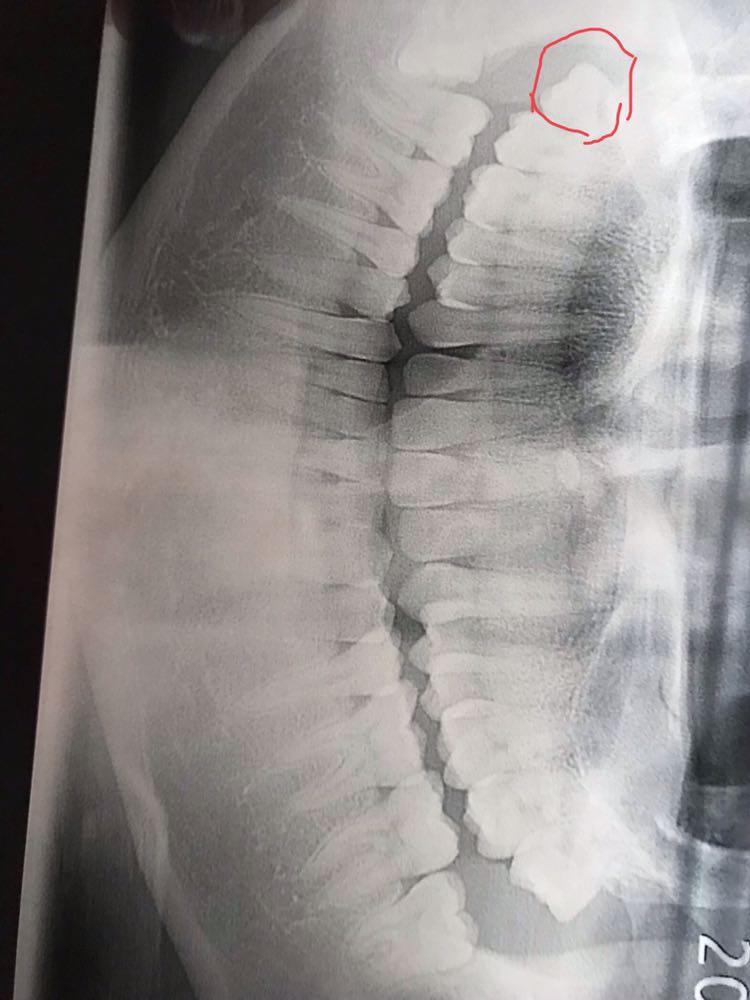

今天刚拔了牙,只拔了一颗。这颗牙有必要拔吗?医生说半个月拔一个,大家帮我看看这颗牙怎么样?拔完牙脸会不会瘦?

拔完牙之后会不会导致脸颊变瘦?两边不均匀?

牙好齐 我今天拔了三颗 没有明显龅牙之类的不会有很大改观的